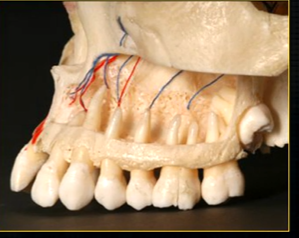

when the thin, surface bone of the maxilla is removed …

can see the roots of the teeth as they are positioned in the alveolar part of the maxilla

the alveolar bone has an internal trabecular, honeycomb appearance - wide enough to envelope all the roots of the posterior teeth